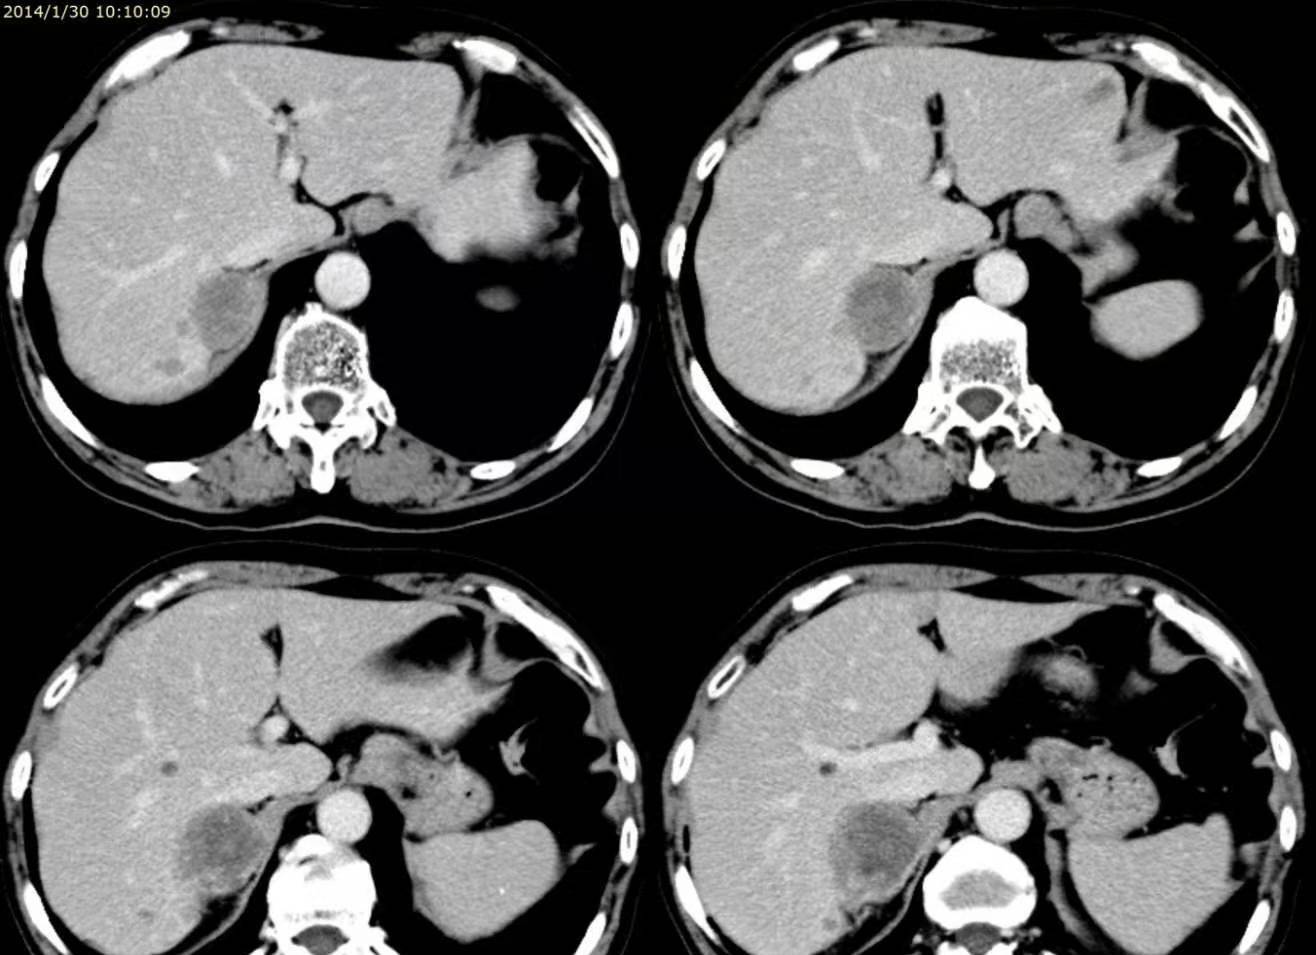

6、心肌活检

若无创检查不能明确诊断 , 应进行侵入性心导管检查和心内膜心肌活检 。 限制型心肌病心导管检查可检测到高心房压伴显著的y波下降 , 在心室压力曲线上有一个早期舒张压下降 , 随后出现高舒张期平台 。 其左心室舒张压通常比右心室高几毫米汞柱 , 与心室压力相等的缩窄性心包炎不同 。

活检可发现心内膜心肌纤维化和增厚 , 心肌被铁或淀粉样蛋白浸润 , 慢性心肌纤维化 , 或Fabry病时血管内皮细胞胞质中有沉积物 。 除非淀粉样变性累及到心外膜的冠状动脉 , 冠状动脉造影为正常的 。 对于RCM最常见的病因应进行实验室检查和其他器官系统的活检(如疑有淀粉样变性者进行直肠活检 , 疑有血色素沉着症者行铁检测或肝活检) 。